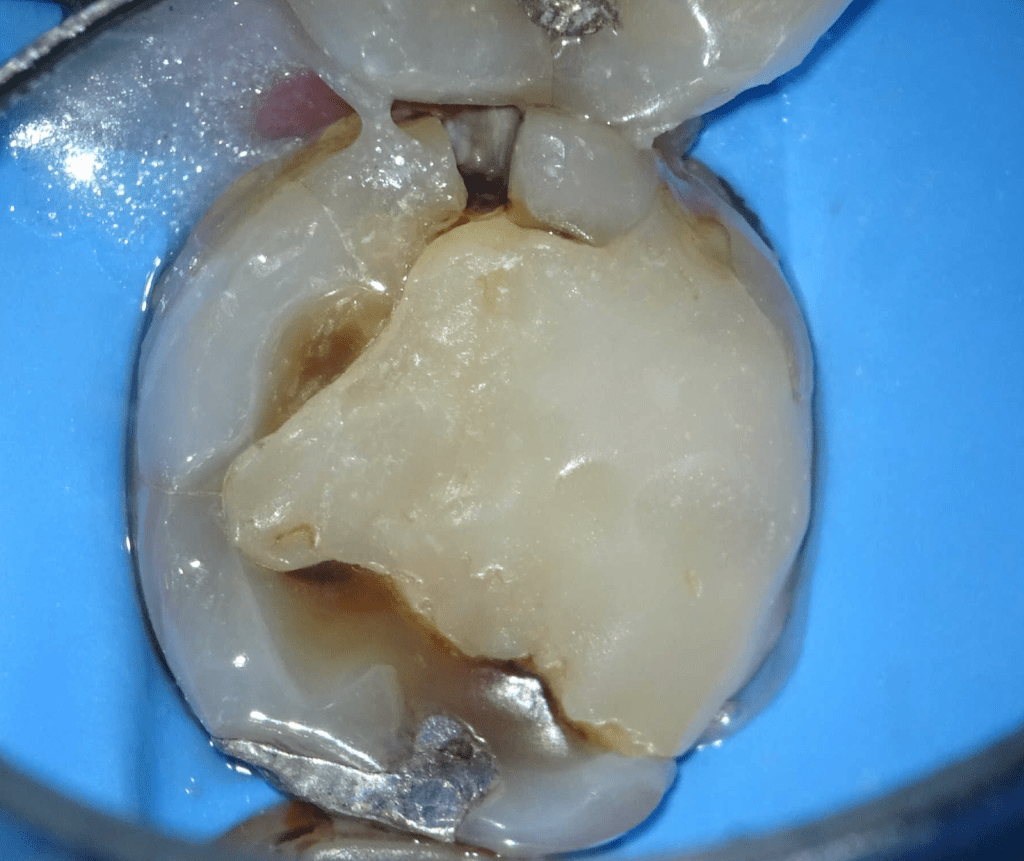

Pulpotomía biodentine + reco preendio